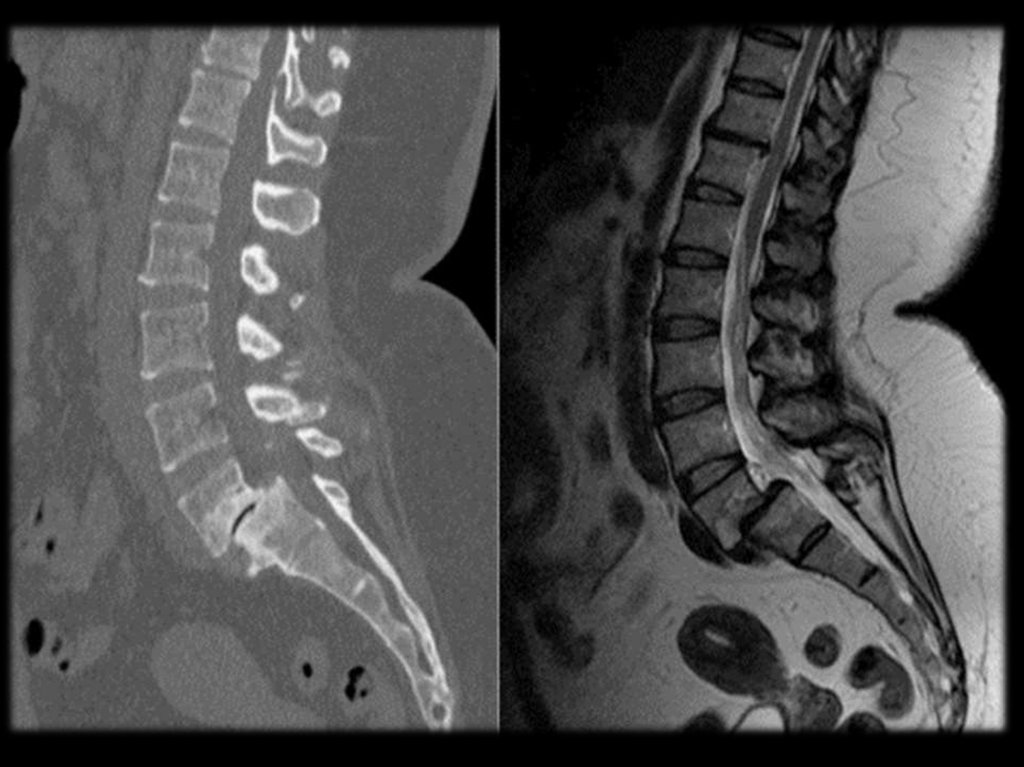

На поясничном уровне наиболее значимы

протрузии и грыжи дисков, а также патология

межпозвонковых суставов.

На поясничном уровне наиболее значимы протрузии и

грыжи дисков, а также патология межпозвонковых

суставов.